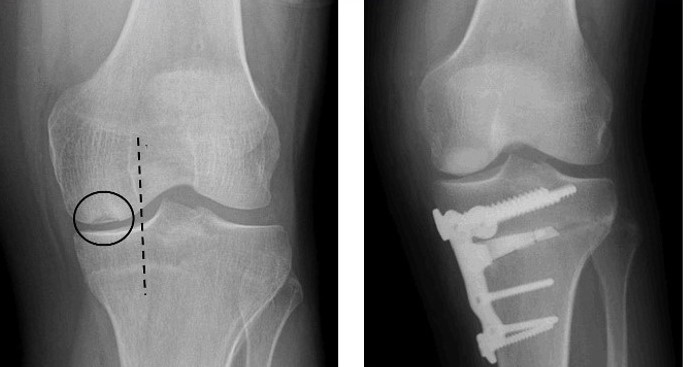

Most osteotomies for knee arthritis are done on the tibia (shinbone) to correct a bowlegged alignment that is putting too much stress on the inner (medial) compartment of the knee.

This procedure can be performed in two different ways:

- A wedge of bone graft or synthetic bone is placed on the inner (medial) side of the tibia and secured with a plate and screws.

- A wedge of bone is removed from the outer (lateral) side of the tibia.

When the surgeon opens the medial wedge or closes the lateral wedge, it straightens the leg. The effect of this is that more load is taken through the joint on the healthy side of the knee, and there is more space between the bones on the damaged, arthritic side. As a result, the knee can carry weight more evenly, easing pressure on the painful side.

- Your surgeon will insert a plate and screws to hold the bones in place until the osteotomy heals.